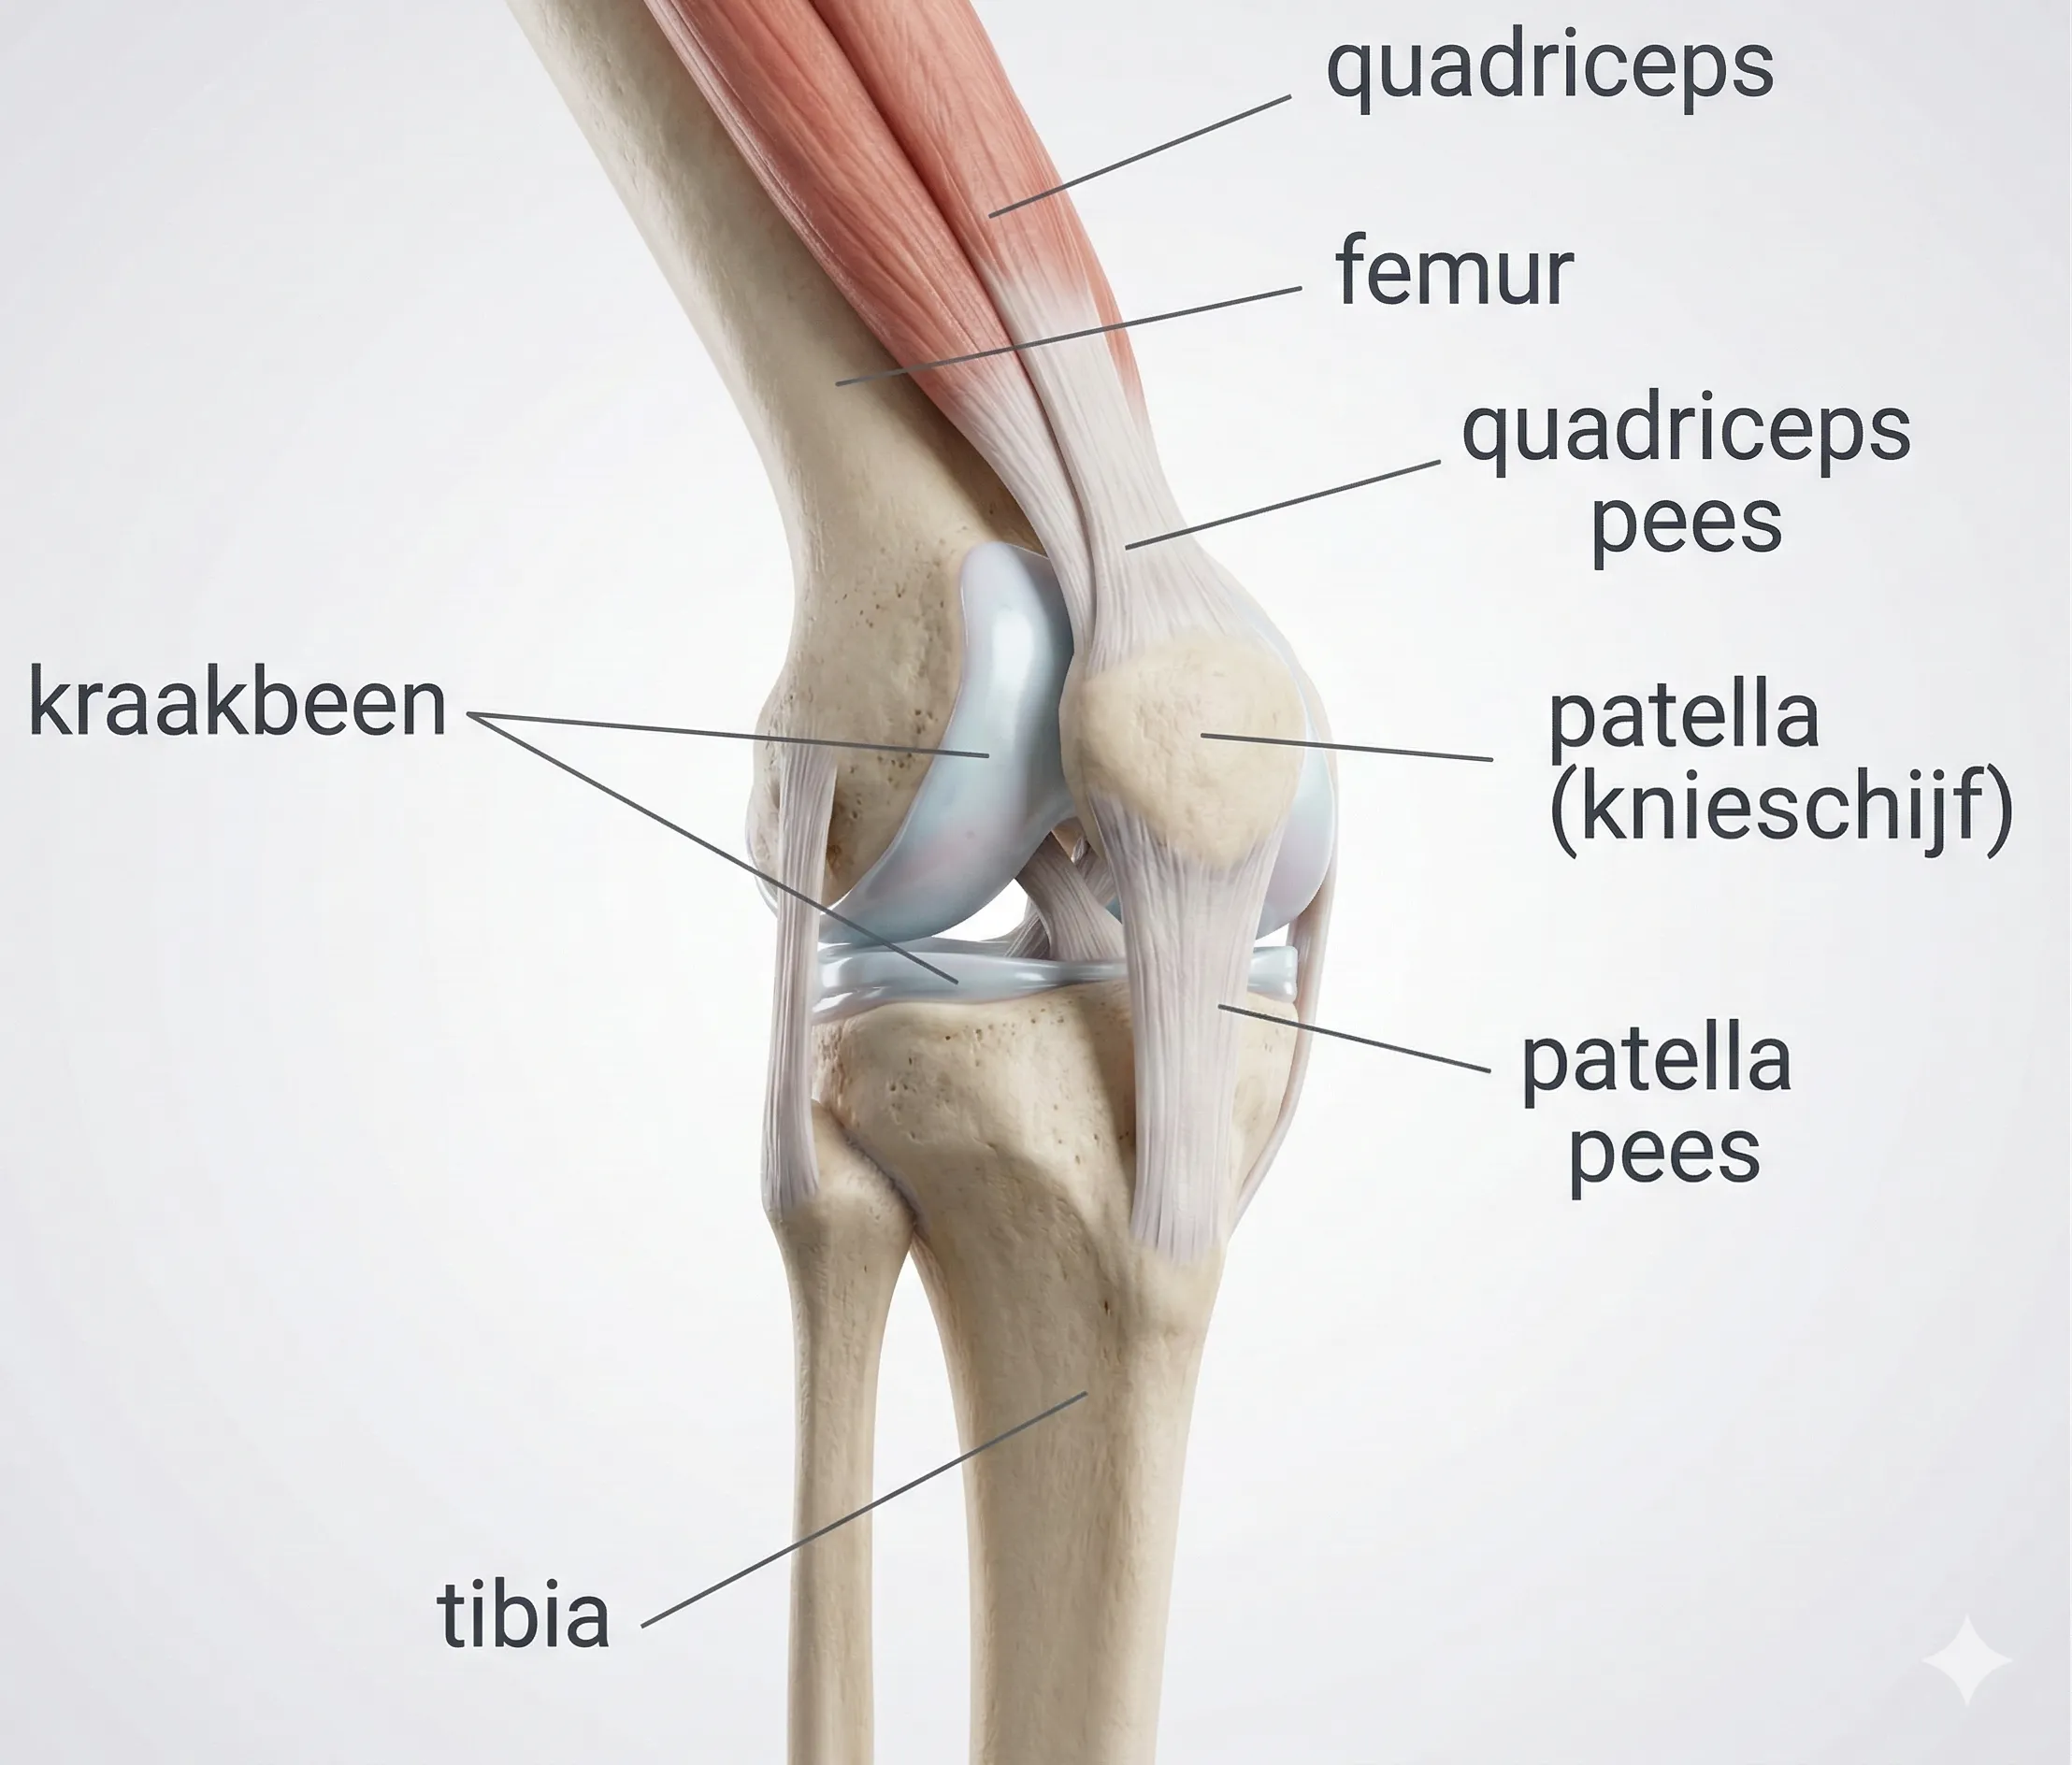

Een tibiaplateaufractuur is een breuk van het bovenste deel van het scheenbeen (tibia) waar het kniegewricht op rust. Dit bovenste gewichtsdragende deel van de tibia heet het tibiaplateau. Deze fractuur kan aan de buitenzijde (laterale tibiaplateau) voorkomen, aan de binnenzijde (mediale plateau) of aan beide zijden tegelijk (bicondylaire fractuur). Het plateau wordt als het ware ingedeukt door de femurcondyl (bovenzijde van de knie) die er bij de impact op drukt. Tibiaplateaufracturen ontstaan meestal door een forse kracht op het kniegewricht – bijvoorbeeld een val van hoogte op gestrekte benen, of een zijdelingse klap tegen de knie. Het zijn ernstige intra-articulaire fracturen, omdat het gewrichtsoppervlak aangedaan is en nauwkeurig herstel vereist om later goed te kunnen functioneren en slijtage te voorkomen.

- Snel optredende zwelling: De knie zwelt binnen korte tijd flink op. Omdat dit een intra-articulaire fractuur is, treedt een hemartrose op (bloeding in het kniegewricht), waardoor de knie gespannen en dik wordt. Daarnaast kan er zwelling aan de onderkant van het bovenbeen en bovenkant van het onderbeen zijn door weefselschade en bloeduitstorting in die regio.

- Pijn en artrose: Omdat het kraakbeen in het kniegewricht een klap heeft gekregen en mogelijk niet perfect glad is achtergelaten, bestaat een verhoogde kans op posttraumatische artrose (slijtage) in de knie op middellange tot lange termijn. Dit betekent dat bijvoorbeeld 5-10 jaar na het letsel slijtageklachten kunnen ontstaan: pijn bij belasten, stijfheid, zwelling na gebruik. Sommige patiënten krijgen last van chronische kniepijn bij traplopen, hurken of weersveranderingen. Bij ernstige artrose kan later een knieprothese overwogen worden.